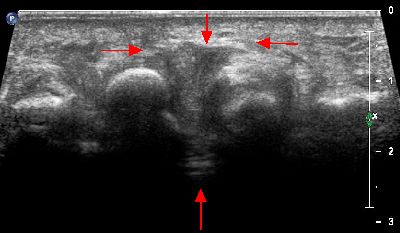

Neuroma di Hauser dell'immagine soprastante con ripresa trasversale Neuroma Hauser ripresa longitudinale